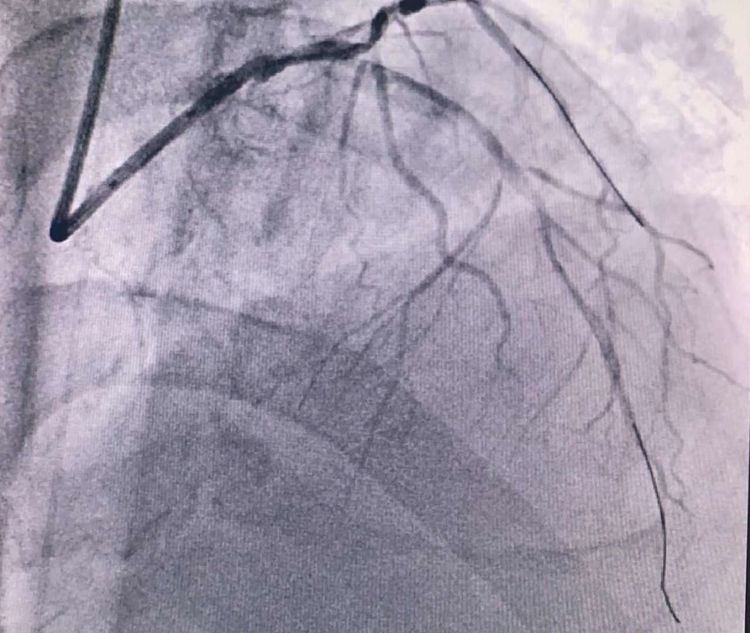

患者前降支、右冠100%閉塞,LCX中段60%狹窄。命懸一線,手術(shù)臺(tái)上持續(xù)胸痛。和患者家屬及時(shí)溝通后,決定行PTCA術(shù)。血壓低至60/40mmHg,在主動(dòng)脈內(nèi)球囊反博的支持下緊急行PCI術(shù)。軌道很快建立,導(dǎo)絲也及時(shí)通過(guò)病變血管,噩夢(mèng)來(lái)了,患者發(fā)生室顫了。在吳棟梁院長(zhǎng)的指揮下,李陽(yáng)主任和心臟團(tuán)隊(duì)的成員共同努力下,除顫、冠脈內(nèi)溶栓、多個(gè)球囊輪流上陣,患者病情平穩(wěn)了,罪犯血管及時(shí)開(kāi)通,血流恢復(fù)三級(jí)血流。平安下臺(tái),準(zhǔn)備擇日再處理冠脈情況。